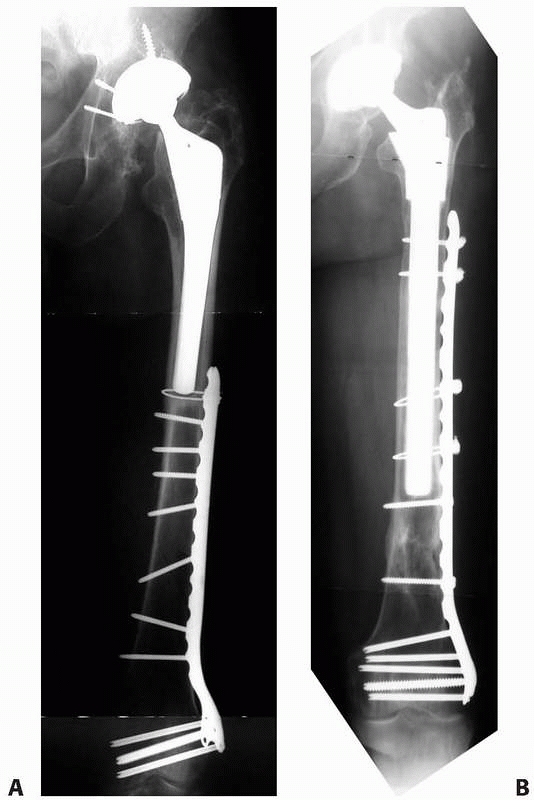

short segment are ill-advised due to inadequate fixation within the

proximal fragment (Fig. 21-11). Ending the plate at (Fig. 21-12)

or just distal to the femoral stem should also be avoided to minimize

the stress rise effect. Additional principles and results of treating

these distal femoral shaft and metaphyseal fractures are presented in Chapters 50 and 51.

![]() |

|

FIGURE 21-12 A.

Ill-advised treatment of a Vancouver type C fracture with a plate that is too short because it creates an unnecessary additional stress riser at the tip of the arthroplasty stem. B. More optimal plate constructs span the entire unprotected zone of the femur. |